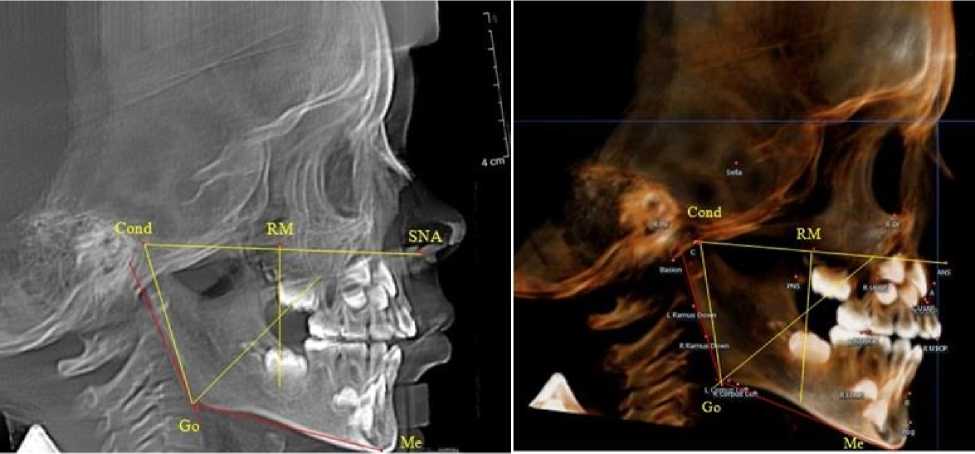

Биссектриса угла Cond-Go-Ме (стресс-ось), так же, как и на ортопантомограмме, располагались позади от формирующихся зачатков первых постоянных моляров нижней челюсти (рис. 4).

Рис. 4. Особенности боковой телерентгенограммы (а) и 3D-модели (б) ребенка 4 лет в периоде прикуса молочных зубов

Зачатки вторых постоянных моляров нижней челюсти располагались кпереди по отношению к биссектрисе угла Go´-Go-Ме, что так же, как и на верхней челюсти, оказывало благоприятное влияние на формирование и прорезывание нижнего первого моляра. При анализе боковых телерентгенограмм и трехмерной модели установлено, что положение зубов и челюстей относительно реперных линий было близким по значениям, полученным при анализе ортопантомограмм. Биссектриса угла Cond-Go-Ме, так же, как и на ортопантомограмме, располагались позади от формирующихся зачатков вторых постоянных моляров нижней челюсти (рис. 6).

а                                     б

Рис. 6. Особенности боковой телерентгенограммы (а) и 3D-модели (б) ребенка 7 лет после прорезывания 1-й группы постоянных зубов

При анализе боковых телерентгенограмм и трехмерной модели установлено, что положе- ние зубов и челюстей относительно реперных линий было близким по значениям, полученным при анализе ортопантомограмм. Биссектриса угла Cond-Go-Ме, так же, как и на ортопантомограмме, располагались позади от формирующихся зачатков вторых постоянных моляров нижней челюсти (рис. 8).

Рис. 8. Особенности боковой телерентгенограммы (а) и 3D-модели (б) ребенка 8 лет после прорезывания постоянных резцов